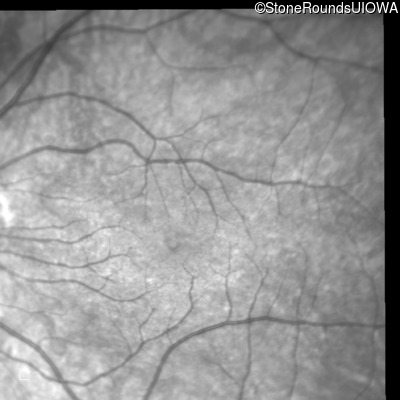

Infrared Fundus Photograph - Right - 10/160 sc

Exemplar